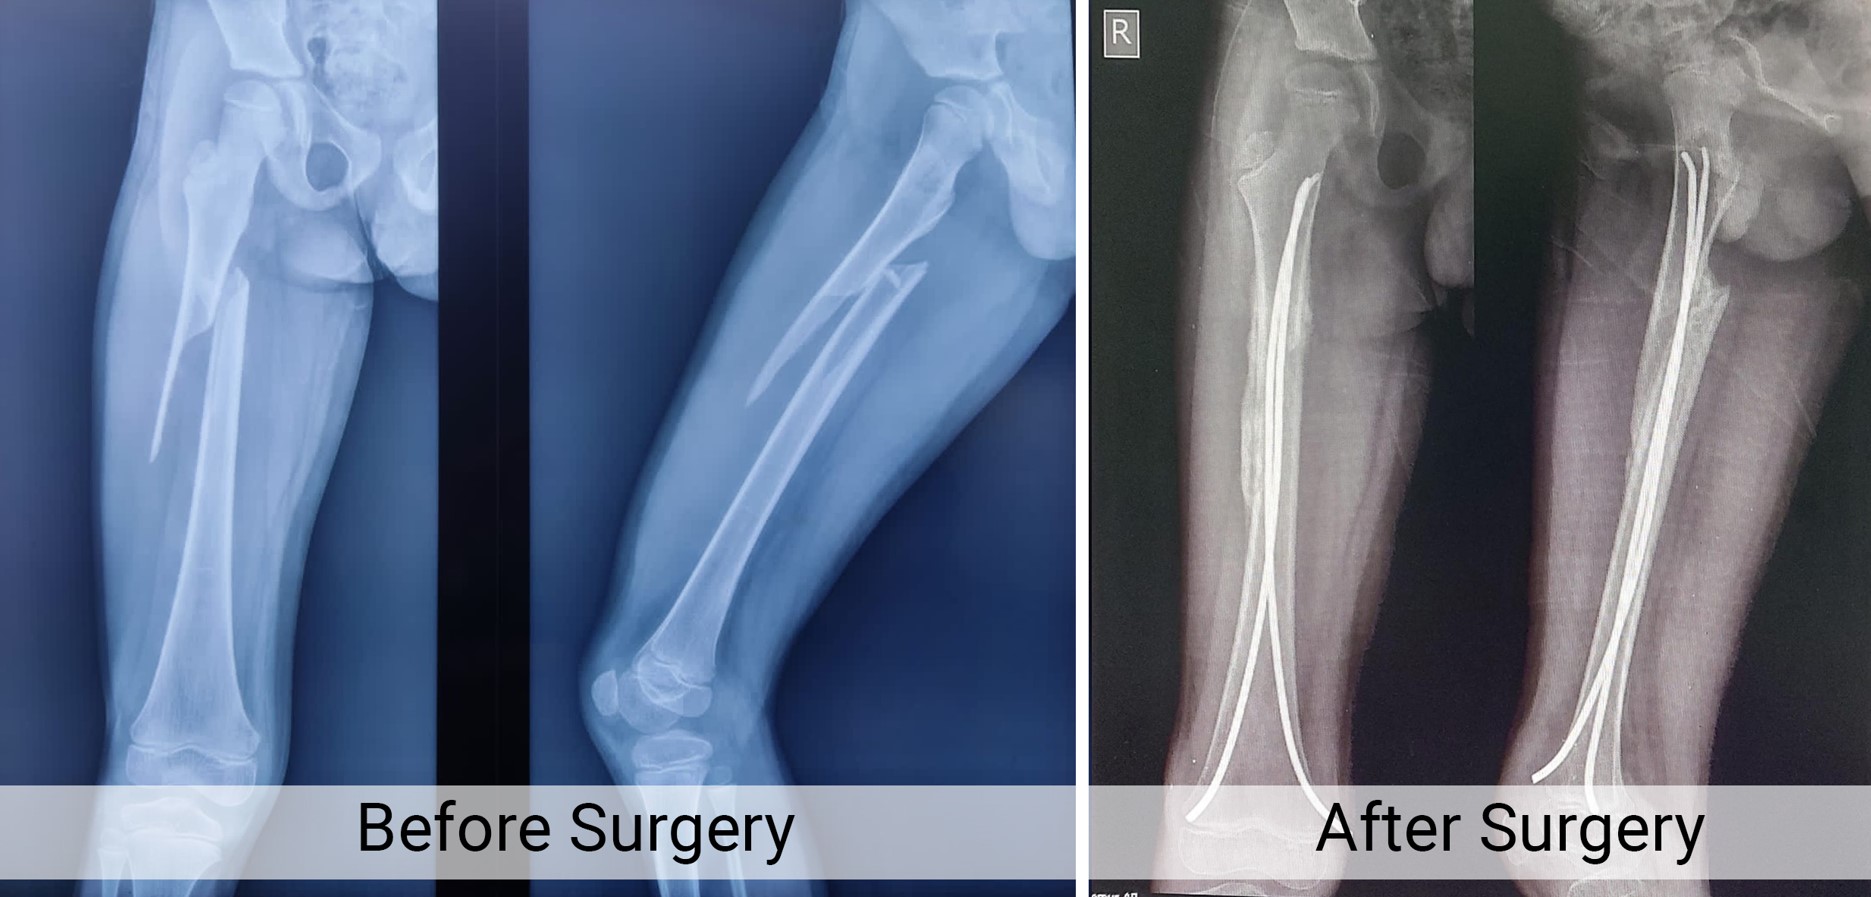

Trauma Fracture